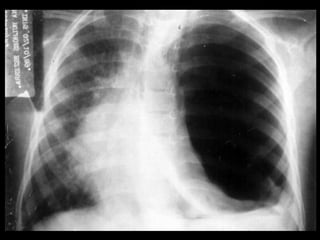

• Diagnóstico – Anamnese –Exame físico – Radiografia de tórax • Inspiração profunda (A) • Expiração profunda – TC de tórax